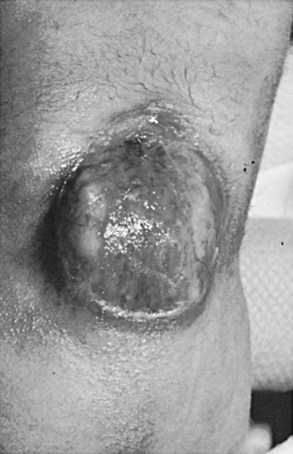

There is a group of congenital defects that affect the formation of the spinal column but do not result in an open vertebral canal (James and Lassman, 1972) (Table 128–4). They occur once in 4000 live births, but with the ease of MRI screening of children with suspected lesions the incidence of these defects is increasing (Bruce and Schut, 1979). In a recent study the incidence of lipomeningocele in families was calculated to be 0.043% (Sebold et al, 2005). These lesions can be very subtle and have no obvious outward signs, but in more than 90% of children there is a cutaneous abnormality overlying the lower spine (Anderson, 1975; Pierre-Kahn et al, 1997). This varies from a small dimple or skin tag to a tuft of hair, a dermal vascular malformation, a very noticeable subcutaneous lipoma, or an asymmetrically curving gluteal cleft (Fig. 128–12). In addition, on careful inspection of the legs, one may note a high arched foot or feet; hammer toes or claw toes; a discrepancy in muscle size, shortness, and decreased strength in one leg compared with the other, typically at the ankle; and/or a gait abnormality, especially in older children (Dubrowitz et al, 1965; Weissert et al, 1989; Jindal and Mahaptra, 2000). Absent perineal sensation, back pain, and secondary incontinence after a period of dryness are common symptoms in older children and young adults (Linder et al, 1982; Yip et al, 1985; Weissert et al, 1989). Lower urinary tract function is abnormal in 40% to 90% of affected older individuals, with the incidence of an abnormality increasing proportionately with age (Mandell et al, 1980; Koyangi et al, 1997; Pierre-Kahn et al, 1997; Sarica et al, 2003). The child may experience difficulty with toilet training, urinary incontinence after an initial period of dryness once toilet trained (especially during the pubertal growth spurt), recurrent urinary infection, and/or fecal soiling. Occasionally, some patients without an obvious back lesion escape detection until they develop urinary (66%) or lower extremity (19%) symptoms or back pain (14%) after puberty caused by delayed traction on the spinal cord (Satar et al, 1995).